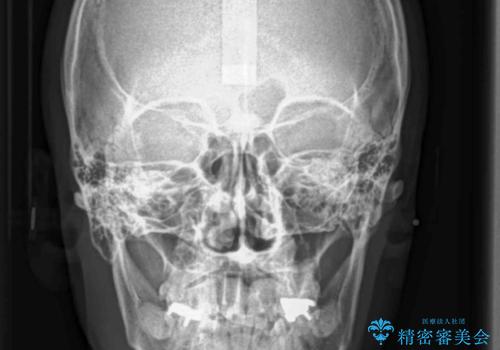

患者様の「できるだけ短期間で治療を終わらせたい、セラミックが入れられたら良いので大がかりなことはしたくない」とのご要望により、3Dシミュレーションを何度も行い患者様とのコンサルを重ね、上顎左右犬歯と左下2を抜歯して②のプランである補綴前矯正(インビザライン)を行うことにしました。

小臼歯の歯根長が長いことを治療前にレントゲンで確認し抜歯部位を決定しました。